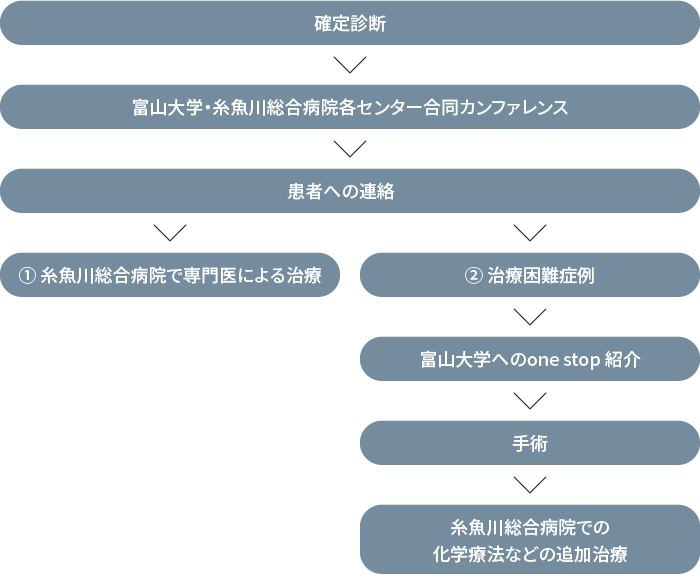

全国でも⼗数か所しかない膵臓切除術年間100症例を超える富⼭⼤学膵臓‧胆道センターと共同して、⽷⿂川地域はもとより富⼭県東部、上越地域をエリアに膵がん、胆道がん、の予後改善を⽬的としております。膵臓‧胆道疾患は胃や⼤腸などの臓器と⽐べて専⾨性が⾼く、内科外科などの専⾨家が連携して治療するため、全ての病院が対応できるわけで

はありません。当院の膵臓‧胆道センターは地域でも⾝近な病院でありながら、⾼度かつ専⾨的な⼿術治療が提供できる環境づくりにも取り組んでいます。

富⼭⼤学附属病院膵臓‧胆道センター‧サテライトとして、富⼭⼤学附属病院で週⼀回開催される肝胆膵キャンサーボード(カンファレンス)にインターネット回線でライブカンファレンス形式で参加し、症例を検討しています。必要な場合には富⼭⼤学附属病院での診断‧治療にもシームレスで移⾏します。

治療進行中は両センター間で治療方針に関しての情報交換が行われ続けます。